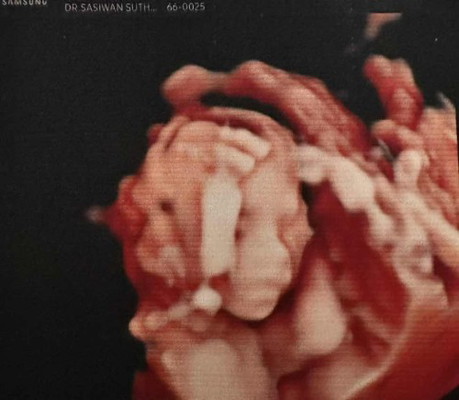

ใครคลอดเดือนกรกฎาคมบ้างคะ อยากสอบถามว่าเลือกคลอดเอง หรือผ่าคลอดกันค่ะ ทางนี้ยังตัดสินใจไม่ได้เลย เพิ่งไปซาวน์มาล่าสุด เริ่มได้เห็นเบบี๋ตัวน้อยชัดขึ้นมาหน่อย แต่คิดหนักว่าควรคลอดแบบไหนดี #ท้องแรกคะ #คุณแม่ๆช่วยแนะนำหน่อยค่ะ

คุณแม่ซาวน์รูปนี้ตอนกี่สัปดาห์คะ อย่กได้แบบนี้บ้าง😂

ตอนซาวน์ในรูปคือ 18 สัปดาห์ค่ะ😊